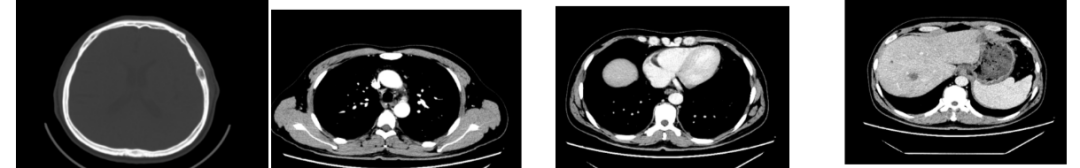

外院CT检查提示:1、两肺多发斑片状、结节影,性质待定,转移瘤?2、纵隔内多发肿大淋巴结;3、肝实质多发稍低密度影,性质待定(转移瘤可能性大)

2018-03-08 PET/CT示:胃癌(?)并全身多发淋巴结转移、肝脏多发转移、双肺上叶多发转移;

△2018-3-19基线CT